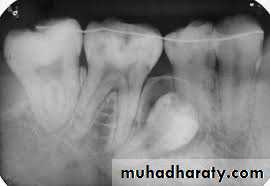

Impacted first and second molars

These are uncommonly impacted, their management consist of surgical extraction through a buccal flap, bone removal avoiding damage to the inferior dental nerve that may cross buccal to the neck of the teeth, sectioning of the tooth may be necessary. The indications of surgical treatment include symptomatic teeth, those that have caused infections, or have evidence of radiographic changes such as cyst or resorption of adjacent teeth roots.Rarely all the three mandibular molars or the second and the third molars are impacted, in this case we start with the mesial of the two and the middle of the three.

Another line of treatment is the surgical up-righting, especially of the impacted second molar. This is done through buccal approach, the tooth is exposed carefully without exposing the CEJ, if the third molar is present it needs to be removed, if not, bone posterior to the second molar is removed, followed by tipping the tooth slightly posteriorly and superiorly, and the tooth can be allowed to erupt spontaneously. This procedure is better carried out when 2/3 of the roots of the impacted second molar are developed. Teeth with fully developed roots have poor prognosis for this procedure

Usually there is no need for fixation but RCT may be needed 6-8 weeks after surgery, also there should be no occlusal forces on the tooth in the postoperative period. Follow up for about 2 years is necessary.